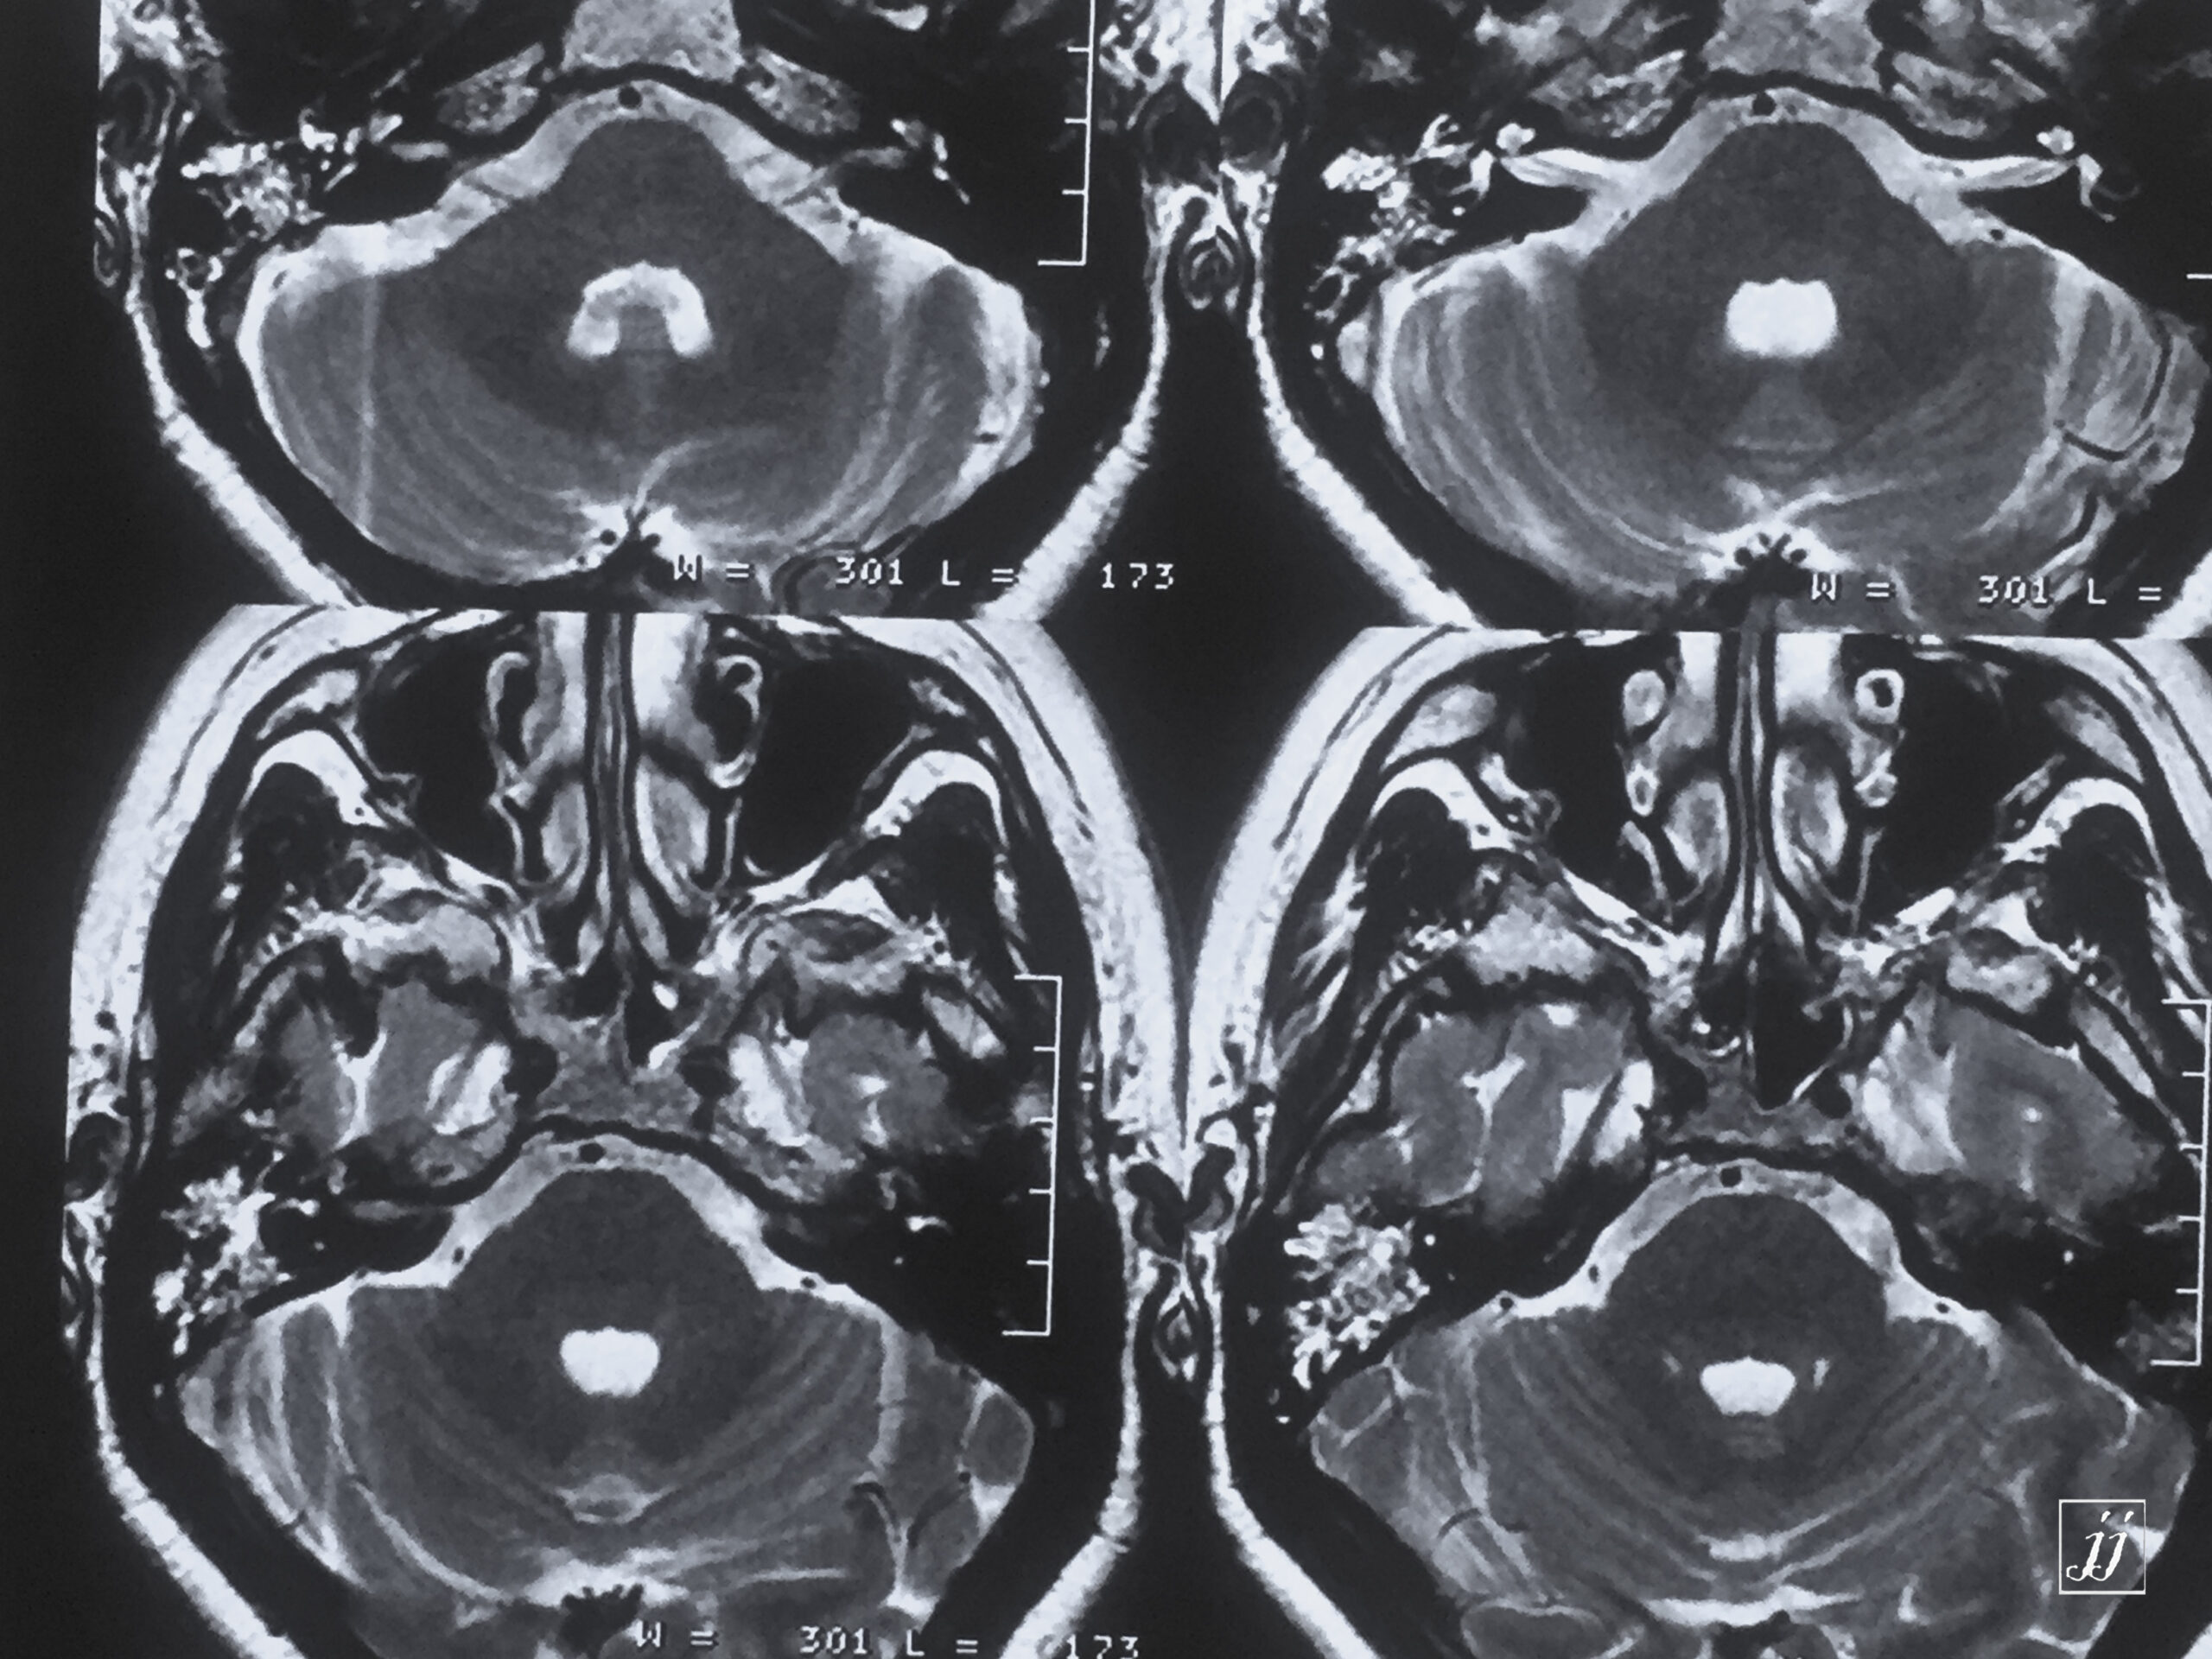

Brain- left glomus jugulars tumor (9)